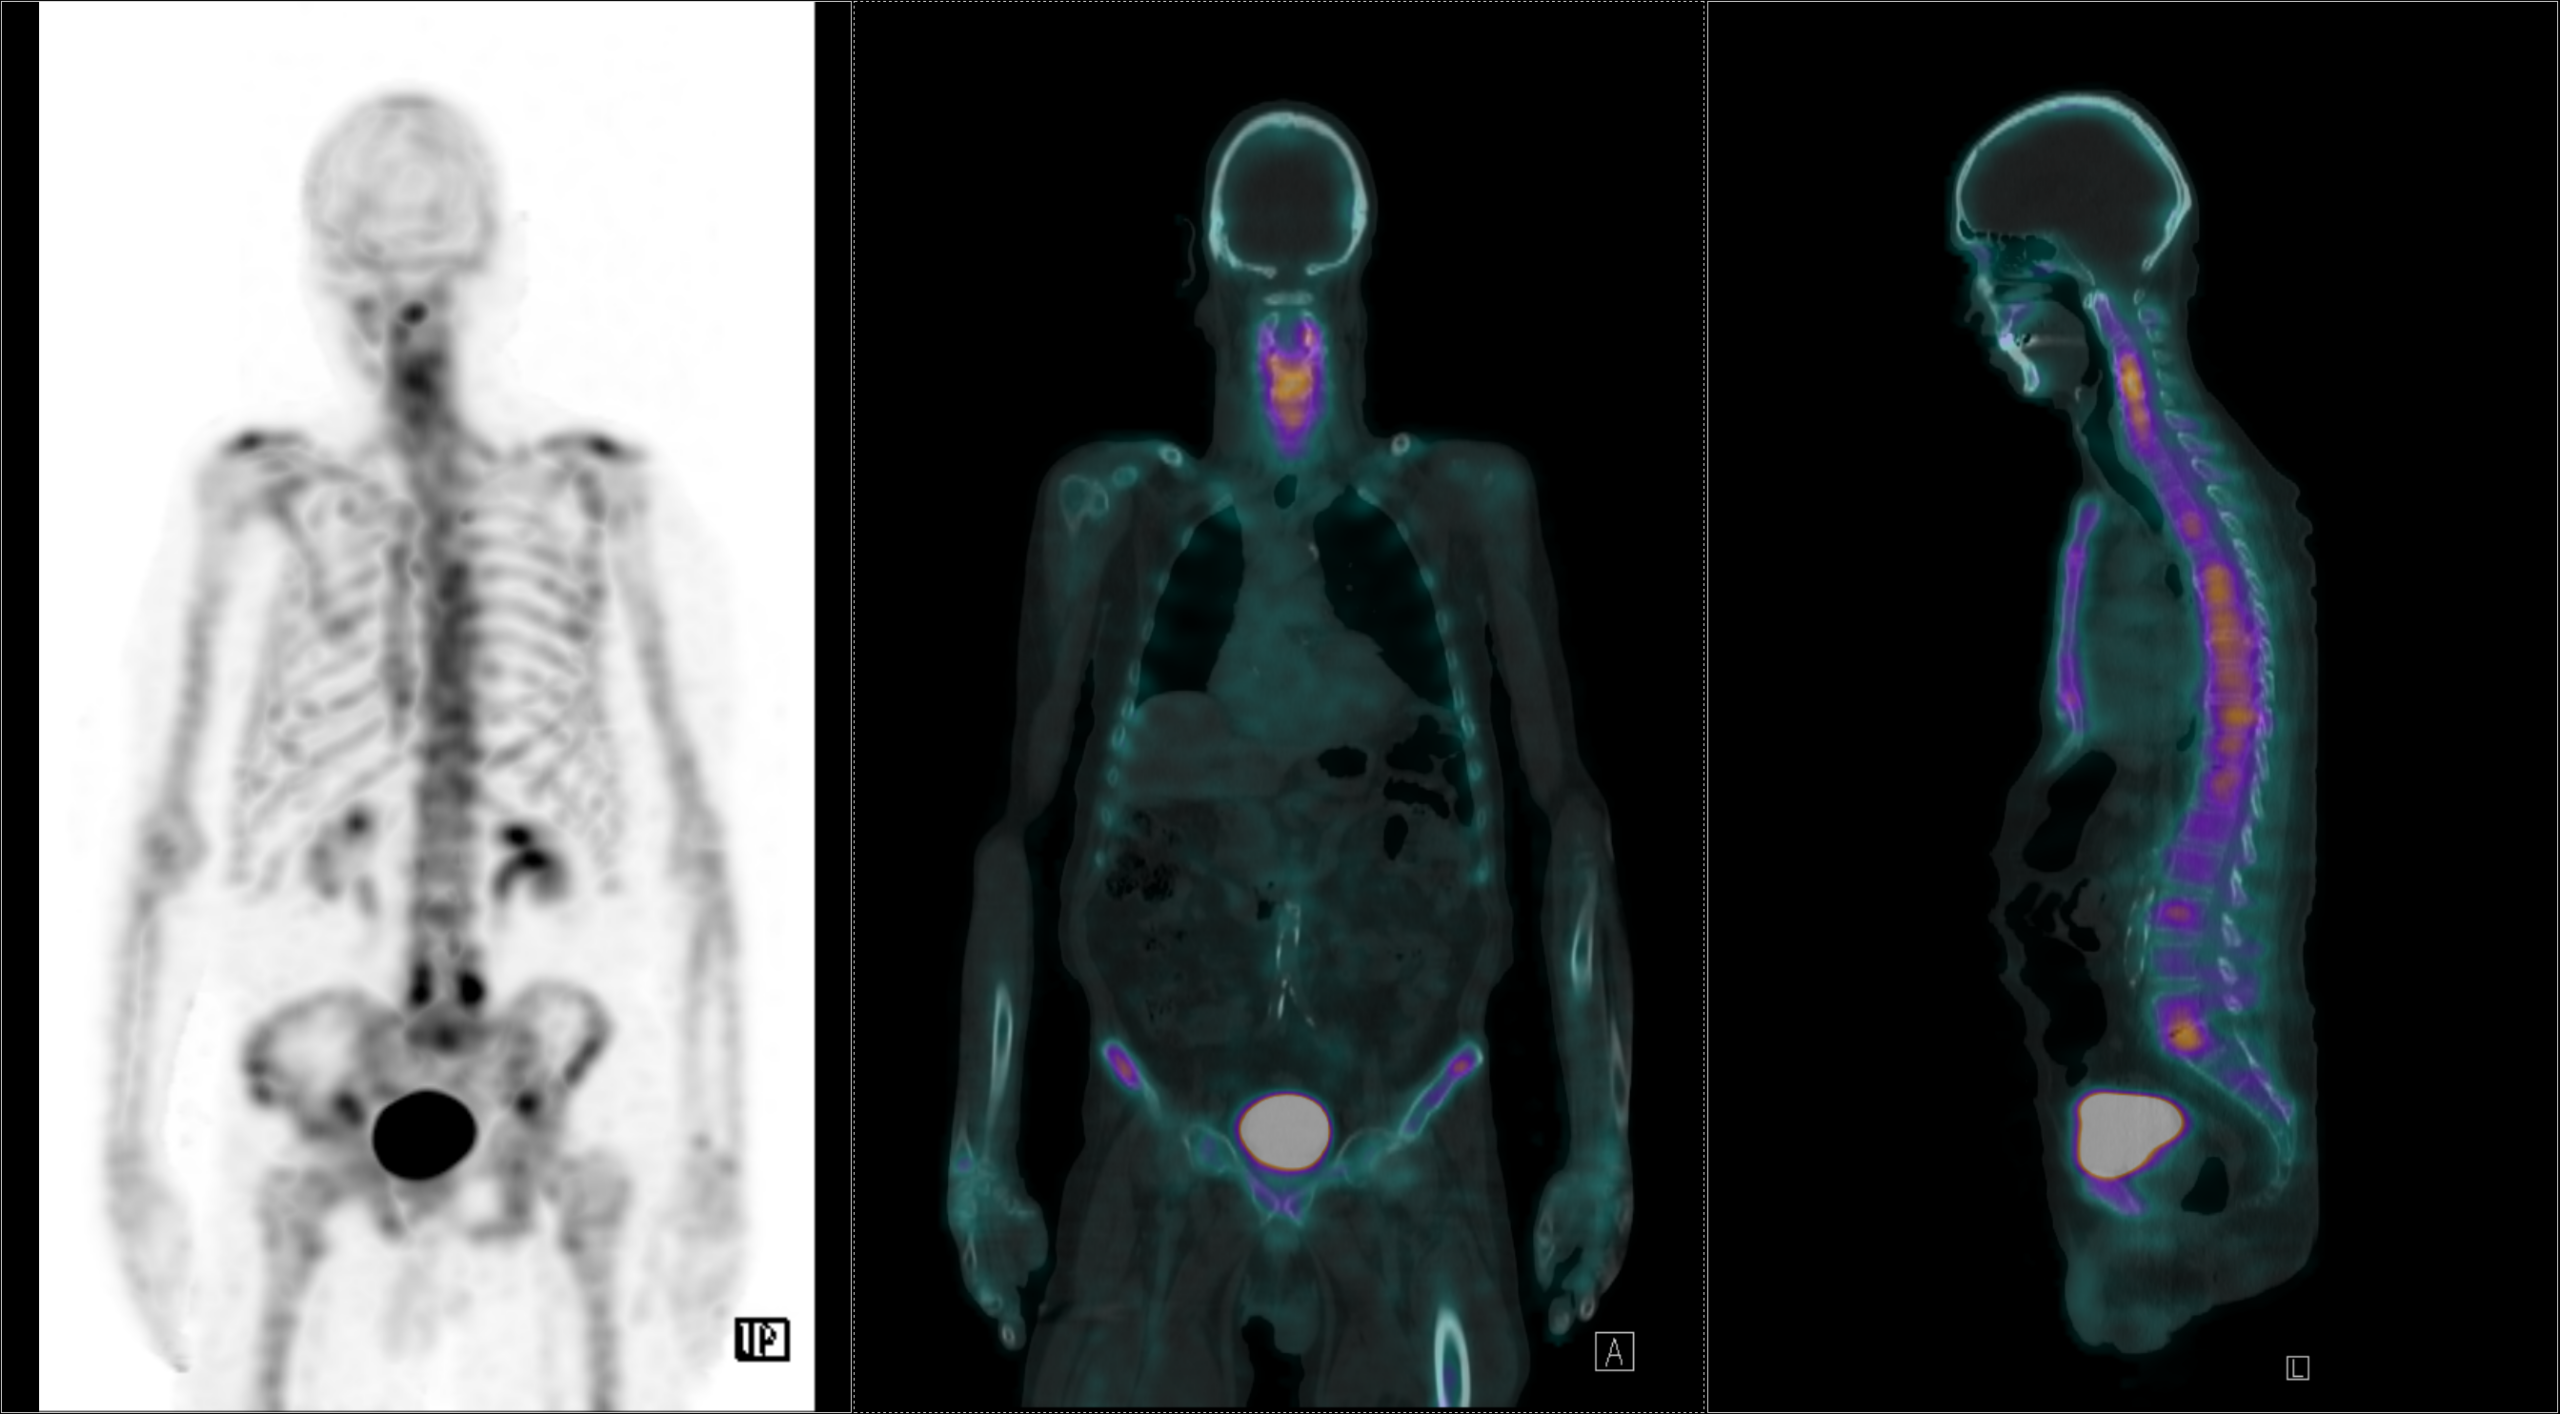

Το Lu-177 PSMA αποτελεί μια στοχευμένη ραδιονουκλιδική θεραπεία για ασθενείς με ορμονοάντοχο μεταστατικό καρκίνο του προστάτη (mCRPC), αξιοποιώντας τη υπερέκφραση του PSMA (Prostate-Specific Membrane Antigen) στα καρκινικά κύτταρα. Προηγείται PSMA PET/CT για ακριβή χαρτογράφηση της νόσου και επιβεβαίωση επαρκούς πρόσληψης του ραδιοφάρμακου. Το Lu-177 PSMA συνδέεται στους PSMA-υποδοχείς, επιτρέποντας στοχευμένη ακτινική δράση υψηλής κυτταροτοξικότητας σε μεταστατικές εστίες οστών και μαλακών μορίων. Η χρήση εξειδικευμένων δοσιμετρικών εργαλείων επιτρέπει την ποσοτική αποτίμηση της δόσης σε κρίσιμα όργανα (π.χ. σιελογόνοι αδένες, νεφροί, μυελός) και στον όγκο, συμβάλλοντας σε εξατομικευμένη θεραπευτική προσέγγιση. Μετά από κάθε κύκλο πραγματοποιείται PSMA PET/CT ή FDG PET/CT (όπου ενδείκνυται), καθώς και στενός αιματολογικός έλεγχος για αξιολόγηση της ανταπόκρισης και των πιθανών τοξικοτήτων. Η θεραπεία έχει αποδειχθεί ιδιαίτερα αποτελεσματική στη μείωση του καρκινικού φορτίου, στη βελτίωση του πόνου, στη μείωση των επιπέδων PSA και στη σημαντική παράταση του προσδόκιμου επιβίωσης σε ασθενείς με εκτεταμένη και ανθεκτική νόσο.